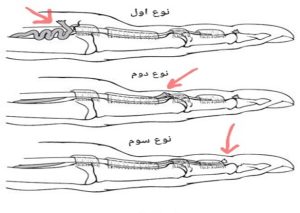

انواع پارگی عضله فلکسور عمقی انگشتان

- نوع اول : جمع شدن تاندون فلکسور عمقی انگشتان در کف دست

- نوع دوم : جمع شدن تاندون فلکسور عمقی انگشتان در مفصل بند اول انگشت (proximal interphalangeal joint)

- نوع سوم : کنده شدن تاندون فلکسور عمقی انگشتان به همراه جدا شدن یک تیکه از استخوان بند آخر انگشت

شکل ۲. انواع پارگی تاندون فلکسور عمقی انگشتان;

در نوع اول مطابق شکل تاندون در کف دست جمع شده است.

در نوع دوم تاندون در مفصل بند اول انگشت جمع شده است.

در نوع سوم علاوه بر جدا شدن تاندون یک تکه از استخوان نیز شکسته و جدا شده است.